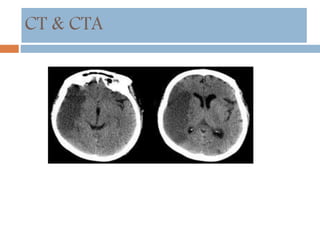

CT & CTA